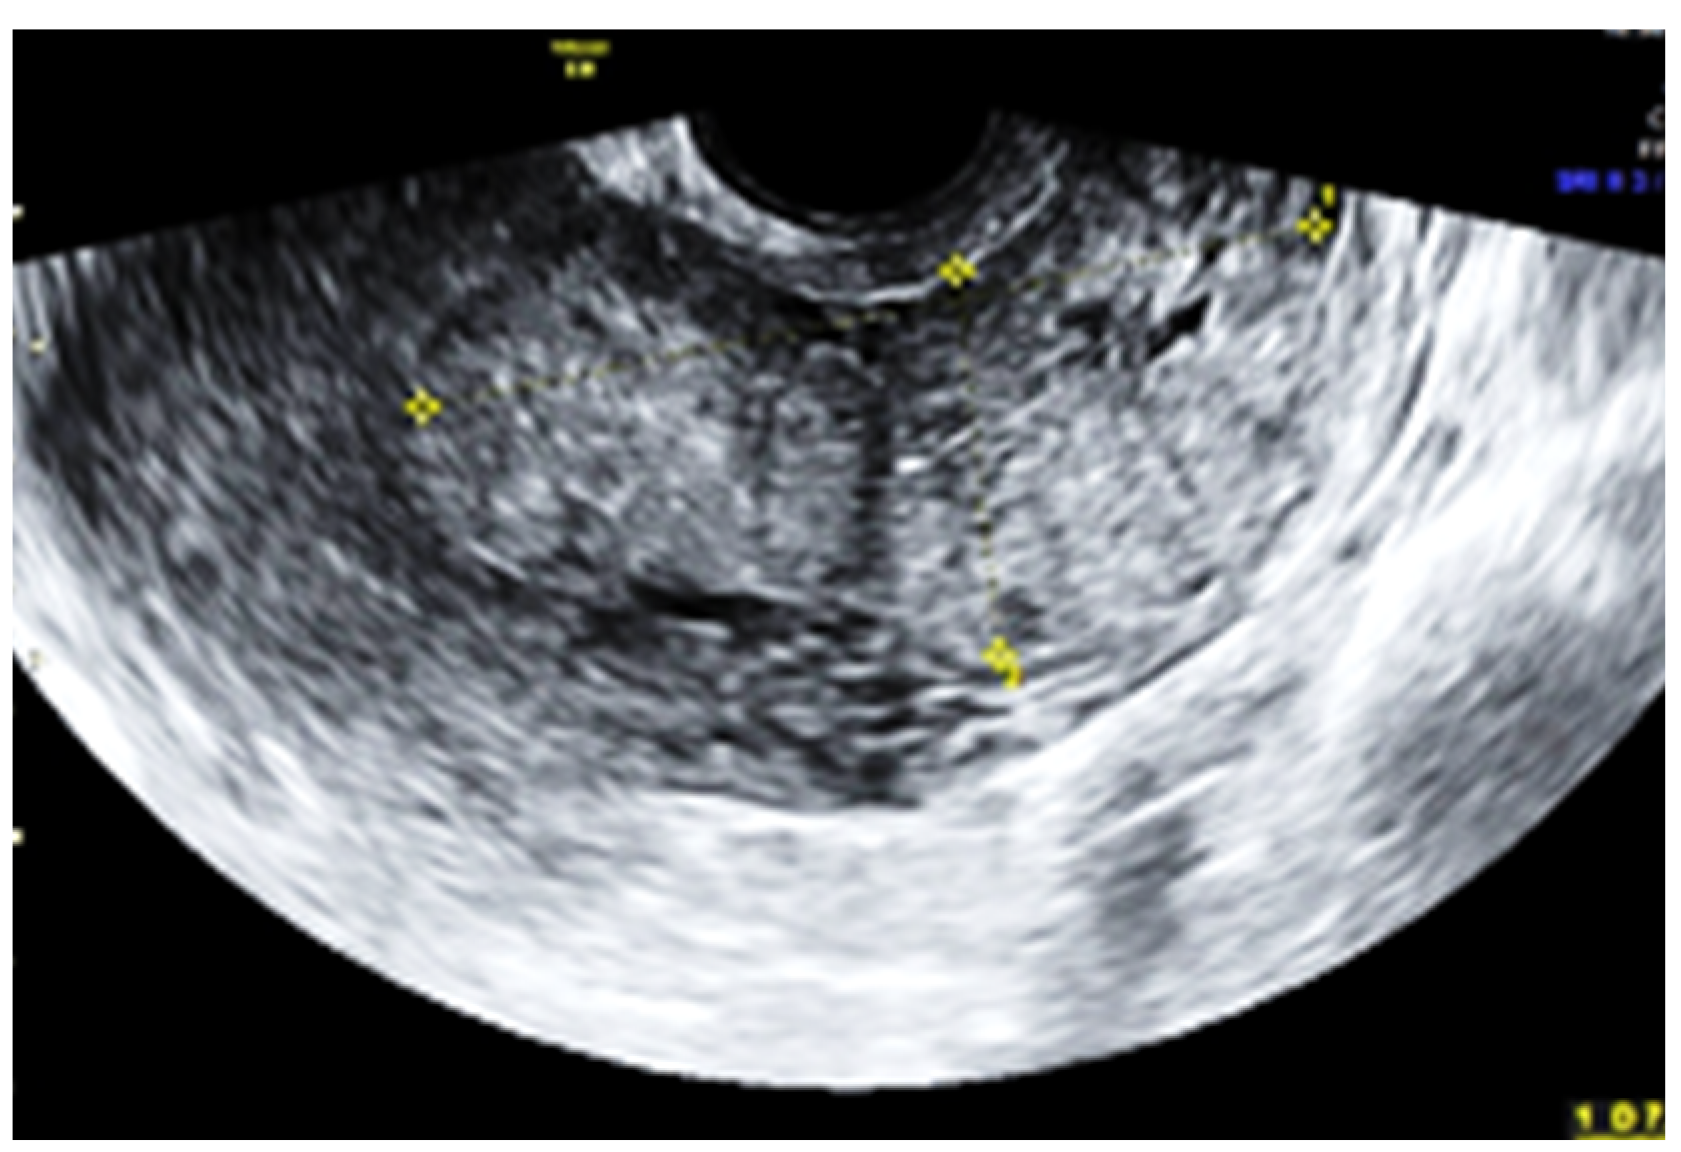

Subsequent ultrasound examination revealed a uterus with a homogeneous structure measuring 67/52/61 mm (Figure 1). However, in the lower portion of the uterine cavity and the upper part of the cervical canal, there was a non-homogeneous hyperechogenic mass measuring 72/30/75 mm (Figure 2). The mass exhibited numerous vessels (Figure 3), while the lower portion of the cervix appeared normal with a length of approximately 13 mm (Figure 4).

Figure 2.

The mass located in the inferior part of the uterus and the upper part of the cervical channel.